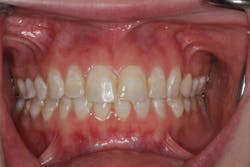

The patient presented with discolored anterior teeth. The teeth had a combination of white spots and brown striations. Tooth No. 9 had an incisal chip (figure 1).

The goal was to make the patient’s smile better for her wedding day, but in a minimally invasive fashion (“don’t drill down my teeth”) and on a limited budget. No small task! She expected us to figure it out and for the results to last over the long term.